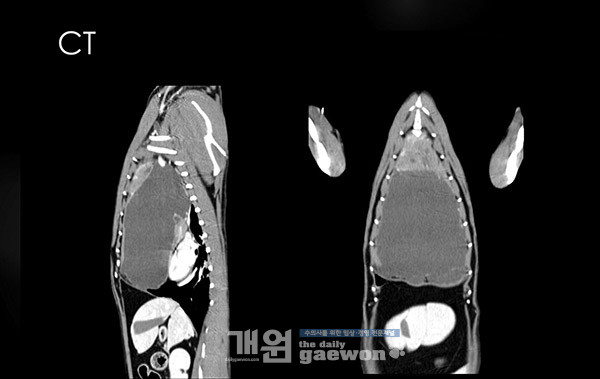

CT검사 결과 전 종격동에 조영 증강된 mass가 보이고, 이 mass로 인해 cyst가 형성된 것을 확인할 수 있었습니다[그림4]. 흉수는 250ml 천자하였고, exudate 양상으로 나왔습니다[그림5]. 흉수 천자 후 방사선 사진은 다음과 같습니다[그림6].